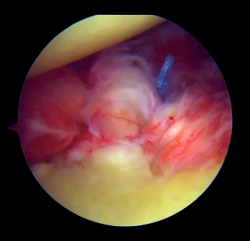

Preparation of the joint (Figure 1)

The patient is placed in lateral decubitus or beach chair position, depending on the preferences of the surgeon. A complete arthroscopic exploration is made through three standard portals, and the lesions are identified. The labrum and anterior capsule are then detached from the 2 to the 6 o'clock position, taking care to preserve their continuity. It is important to perform carefully detach labrum from the glenoid rim and remove all soft tissue until de muscle fibres of the subscapularis muscle and base of the coracoid are visualised. This will make easier the introduction of the graft and the creation of a flat bony surface to accommodate the graft.

Figure 1. View from the anterosuperior portal (left shoulder). Note the flat glenoid surface after drilling and roughening of the glenoid bed and deinsertion of the anteroinferior capsulolabral complex.

We then address the bone defect: with the glenoid defect exposed, the defect is evened, with drilling and roughening of the glenoid cavity neck until a flat and uniform surface is obtained on which to position the graft. The central point of the defect is selected for positioning of the graft, and an implant is inserted as a reference that subsequently will be used for capsulolabral repair.